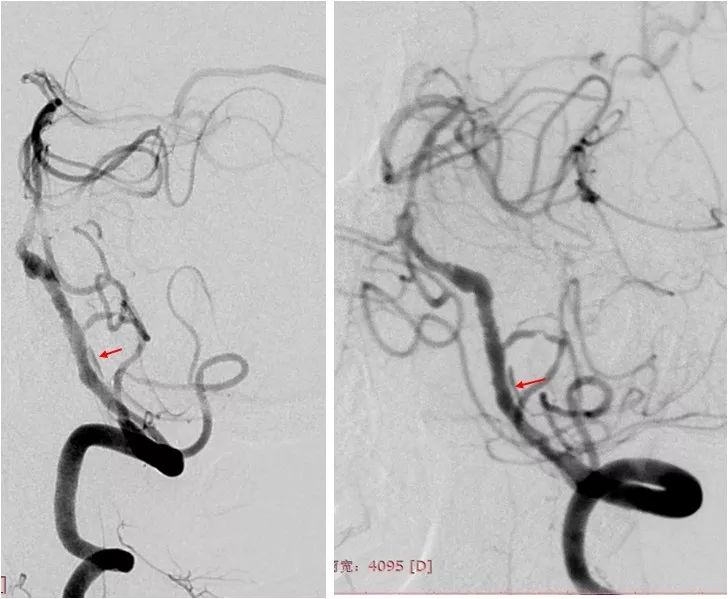

MRA:双侧胚胎型大脑后动脉;左椎动脉优势,V4段重度狭窄(图2)。

图2

DSA:右颈内动脉C6段重度狭窄;双侧胚胎型大脑后动脉;左椎动脉V1段迂曲,V4段重度狭窄;右椎动脉纤细,V4段以远显影欠佳(图3-6)。

全麻下右股动脉入路,将6F导引导管至左椎动脉V2段。 造影显示左椎动脉V4段重度狭窄(图7)。

遂以大于命名压的压力后扩张支架。其后造影显示支架处无明显残余狭窄,支架近心端管壁侧后方见局部造影剂滞留,考虑血管夹层(红箭)(图10)。